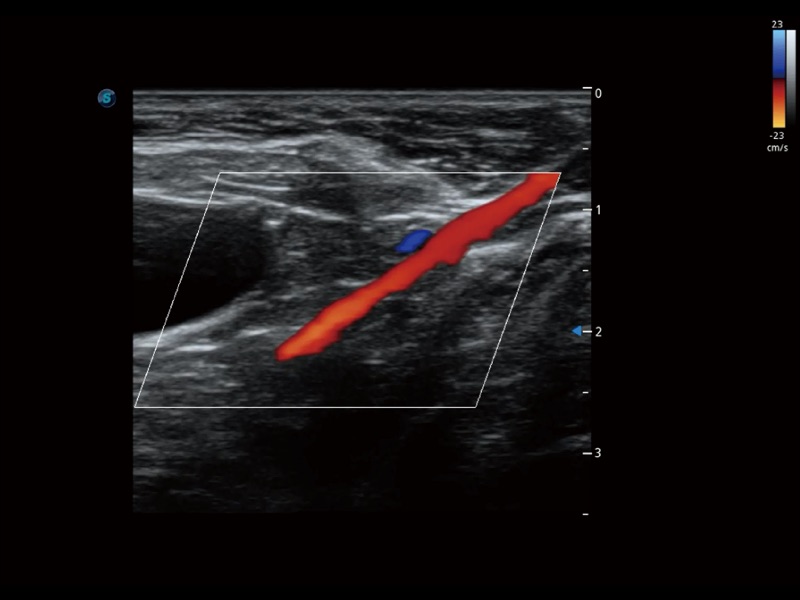

通過創(chuàng)新的 Matrix E自適應(yīng)濾波器和超長(zhǎng)時(shí)間域算法,極大提升超低速微細(xì)血流的檢出能力,同時(shí)更精準(zhǔn)地濾除軟組織和噪聲信號(hào),為獸用醫(yī)生提供以往無法通過常規(guī)血流獲得的疾病診斷信息。

通過色彩血流和實(shí)時(shí)寬景相結(jié)合,可觀察到完整的靜脈或動(dòng)脈的血流,方便醫(yī)生檢查。實(shí)時(shí)掃查過程中,如有任何操作失誤也可以很容易地進(jìn)行回掃擦除,而不會(huì)中斷掃查。